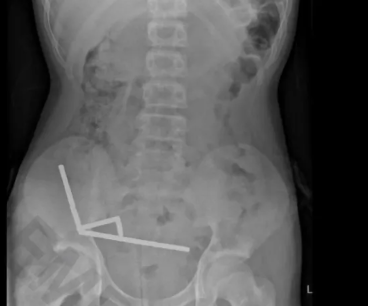

陶朗加一名13岁男孩因吞下多达100颗高强度磁铁,紧急送医并接受了重大手术。

手术中,医生不得不切除部分肠道,同时取出所有磁铁。

陶朗加医院普通外科顾问Nicola Davis表示,磁铁在肠道内相互吸引,造成肠道组织撕裂甚至穿孔,风险极高。

这名丰盛湾男孩在入院时,仅抱怨腹痛,但随后透露,一周前他吞下了80到100颗钕磁铁。